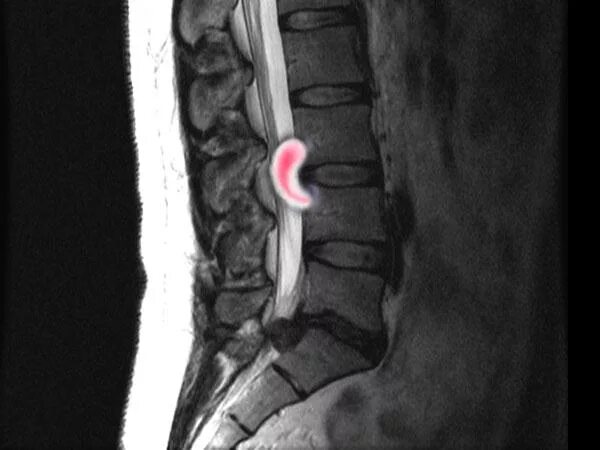

Мрт шейно поясничного отдела